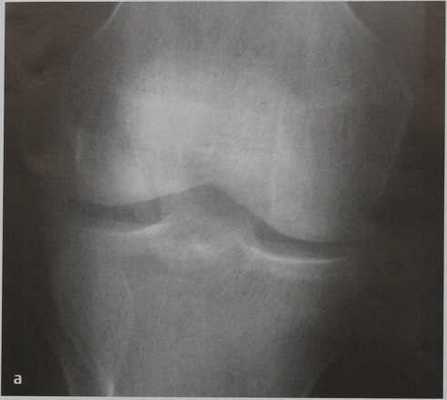

(Слева) Рентгенография коленного сустава в передне-задней проекции: определяется перелом нижней поверхности надколенника с отсутствием смещения. Переломы с отсутствием смещения зачастую проще визуализировать в передне-задней проекции чем переломы со смещением.

(Справа) При рентгенографии в боковой проекции у этого же пациента определяется поперечный перелом нижней поверхности надколенника с отсутствием смещения. Поперечные переломы иногда возникают вследствие насильного разгибания при сокращении четырехглавой мышцы. (Слева) На рентгенографии в передне-задней проекции определяется продольный перелом надколенника вследствие прямого удара. Острые края перелома позволяют отличить такую травму от надколенника, состоящего из двух частей.

а, b Поперечный закрытый перелом надколенника. Рентгенологическое исследование надколенника в прямой (а) и боковой(b) проекциях.